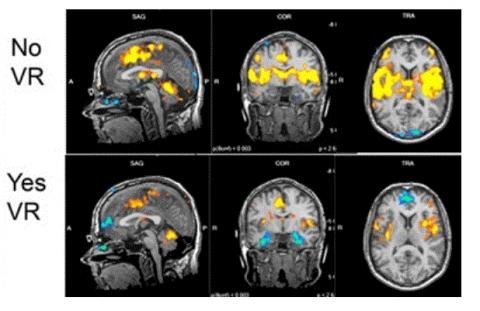

이들은 신체의 33% 이상 덮는 심한 화상을 앓고 있는 환자에게 VR 게임을 체험시키면서, 그 효과를 분석했다. 그 결과 환자는 VR 게임을 한 후 통증 관련 뇌 활동이 현저히 감소하는 모습을 보였다.

MRI 뇌 스캔 사진. 연구진은 SnowWorld를 통해 게임을 한 환자의 통증 관련 뇌 활동이 현저히 감소했다고 밝혔다. ⓒ University of Washington